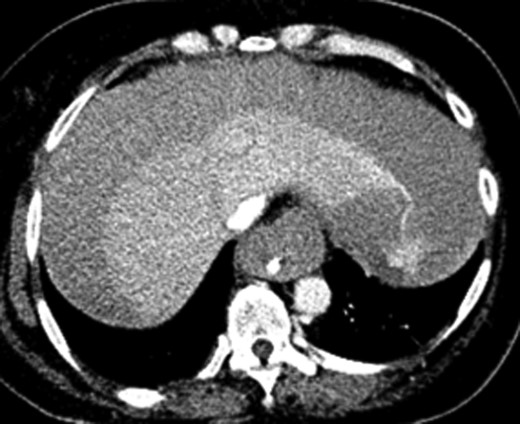

Once stable, imaging confirmed PE (Fig. 2) with a RV to left ventricle (LV) ratio of 2.1 (Fig. 3). The patient was then admitted to the ICU requiring inotropic support. Approximately 4 h later, the patient had concerning features of abdominal compartmental syndrome with increase abdominal distention and bladder pressures >25 mmHg was noted. Repeat imaging showed large volume hemoperitoneum emanating from the left hepatic lobe (Fig. 4). The patient underwent a decompressive laparotomy with a non-anatomic liver resection of segments I and II and temporary abdominal closure. Due to concerns of distal limb ischemia of the arterial cannulation site, an 8-Fr reperfusion cannula was placed in the left superficial femoral artery (SFA).

CTA chest showing significant pulmonary embolic clot burden occluding the right and left upper lung lobes.